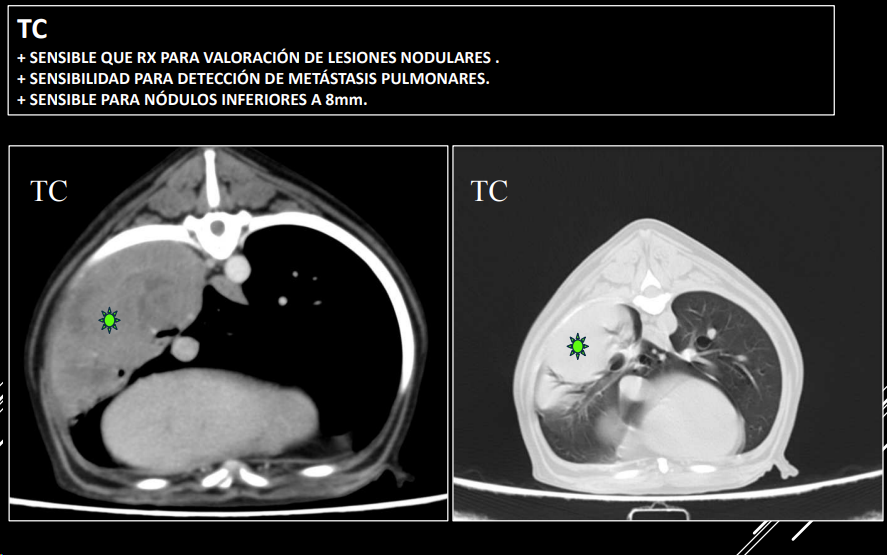

APLICACIONES DEL TC

- Siempre empezamos por una radiografia, ya luego tomogrofia o TC (Al ser mas caro y siendo generalmenta la mayoria de problemas diagnosticables con radiografia)

- Exploraciones radiográficas inconcluyentes.

- Ampliar información de estudios radiográficos.

- Diferenciar entre lesión mediastínica, pulmonar, pleural o pared torácica.

- Detectar metástasis de pequeño tamaño o tromboembolismos pulmonares.

- Evaluar la lesión previo a cirugía.

- Toma de biopsias guiada.